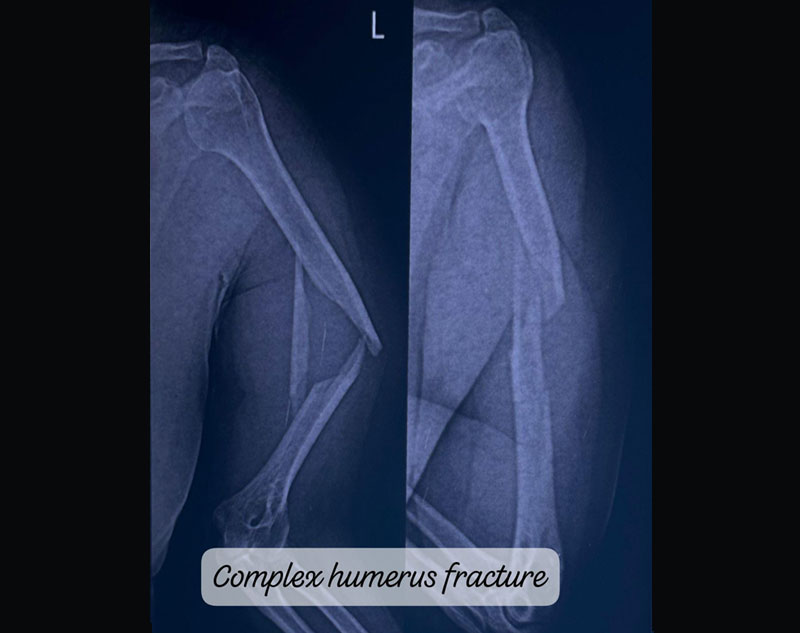

Complex Trauma in orthopedics refers to severe injuries involving multiple or complicated fractures, often combined with soft tissue damage.

These injuries may involve:

Treatment for complex trauma requires a multidisciplinary approach, including surgical intervention, internal/external fixation, and sometimes reconstruction of damaged tissues.